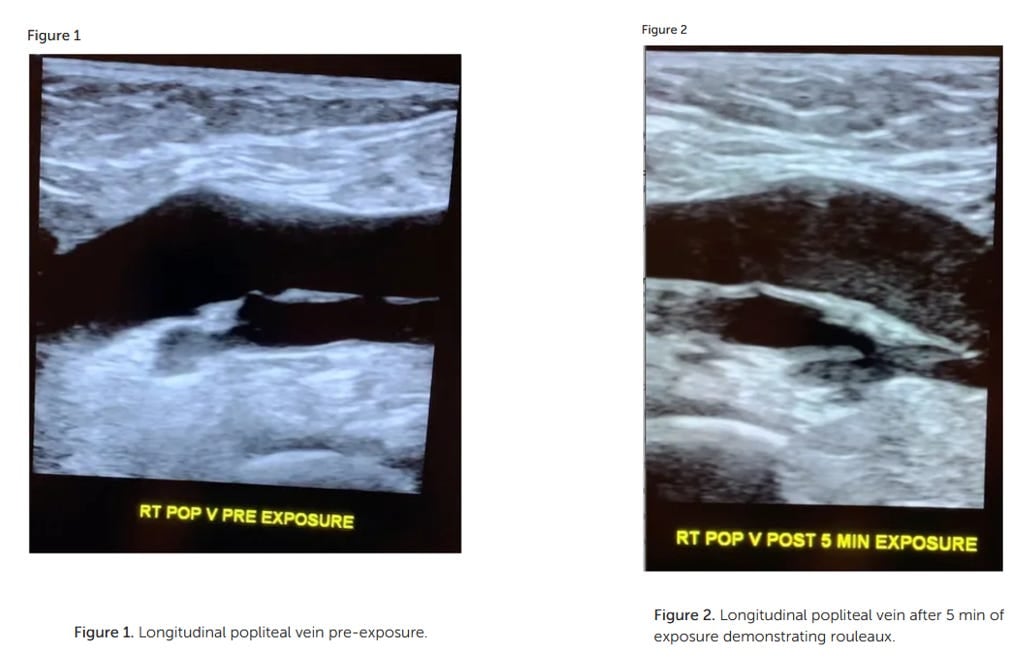

Smart Phone Exposure Shows Rouleaux Formation Via Ultrasound In Large Leg Veins Within Minutes And New Guidelines For Safe Exposure For Kids To Smart Devices - Age 0-6 No Screen Time Is Safe!

by Ana Maria Mihalcea, MD, PhD

Hypothesis: ultrasonography can document dynamic in vivo rouleaux formation due to mobile phone exposure

This case report shows rouleaux formation in a leg vein after cell phone exposure via ultrasound. Live blood analysis is also a great way to show immediate rouleaux formation with exposure to smart phones. It also enhances the growth of the filaments and microchips in the blood - ultimately these blood changes increase the risk of blood clots and diminish oxygen delivery capacity of the red blood cells.